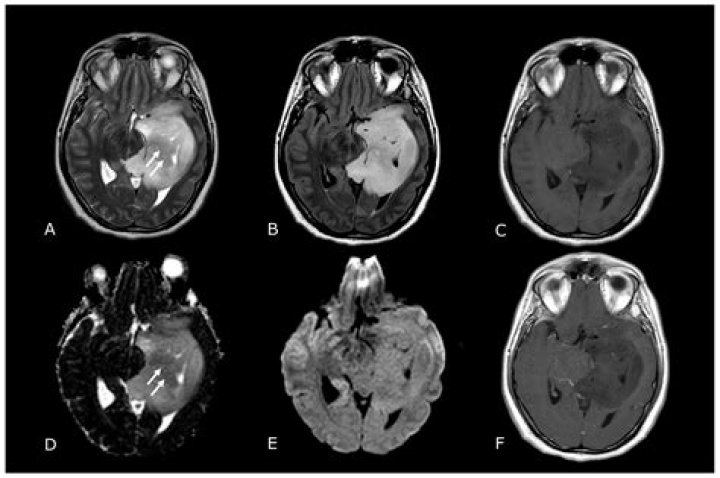

Cranial computed tomography (CT) and magnetic resonance imaging (MRI) with and without contrast media are widely used for primary diagnosis of brain tumor...